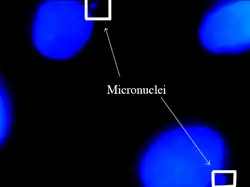

Micronuclei are characterized in the cells that have some sort of DNA damage. This includes damage caused by radiation, harmful chemicals, and random mutations that occur throughout the genome. Micronuclei are small bodies that can be seen budding off of a newly divided daughter cell. Micronuclei can contain a whole chromosome or part of a chromatid. The increased formation of micronuclei is usually an indication of increased DNA damage or mutation. It is characteristically found in cancer cells, or cells that have been exposed to increased risk factors.

Micronuclei are often overlooked in cancer diagnosis and treatment. If observed, they are viewable under a microscope and often located next to other larger nuclei.